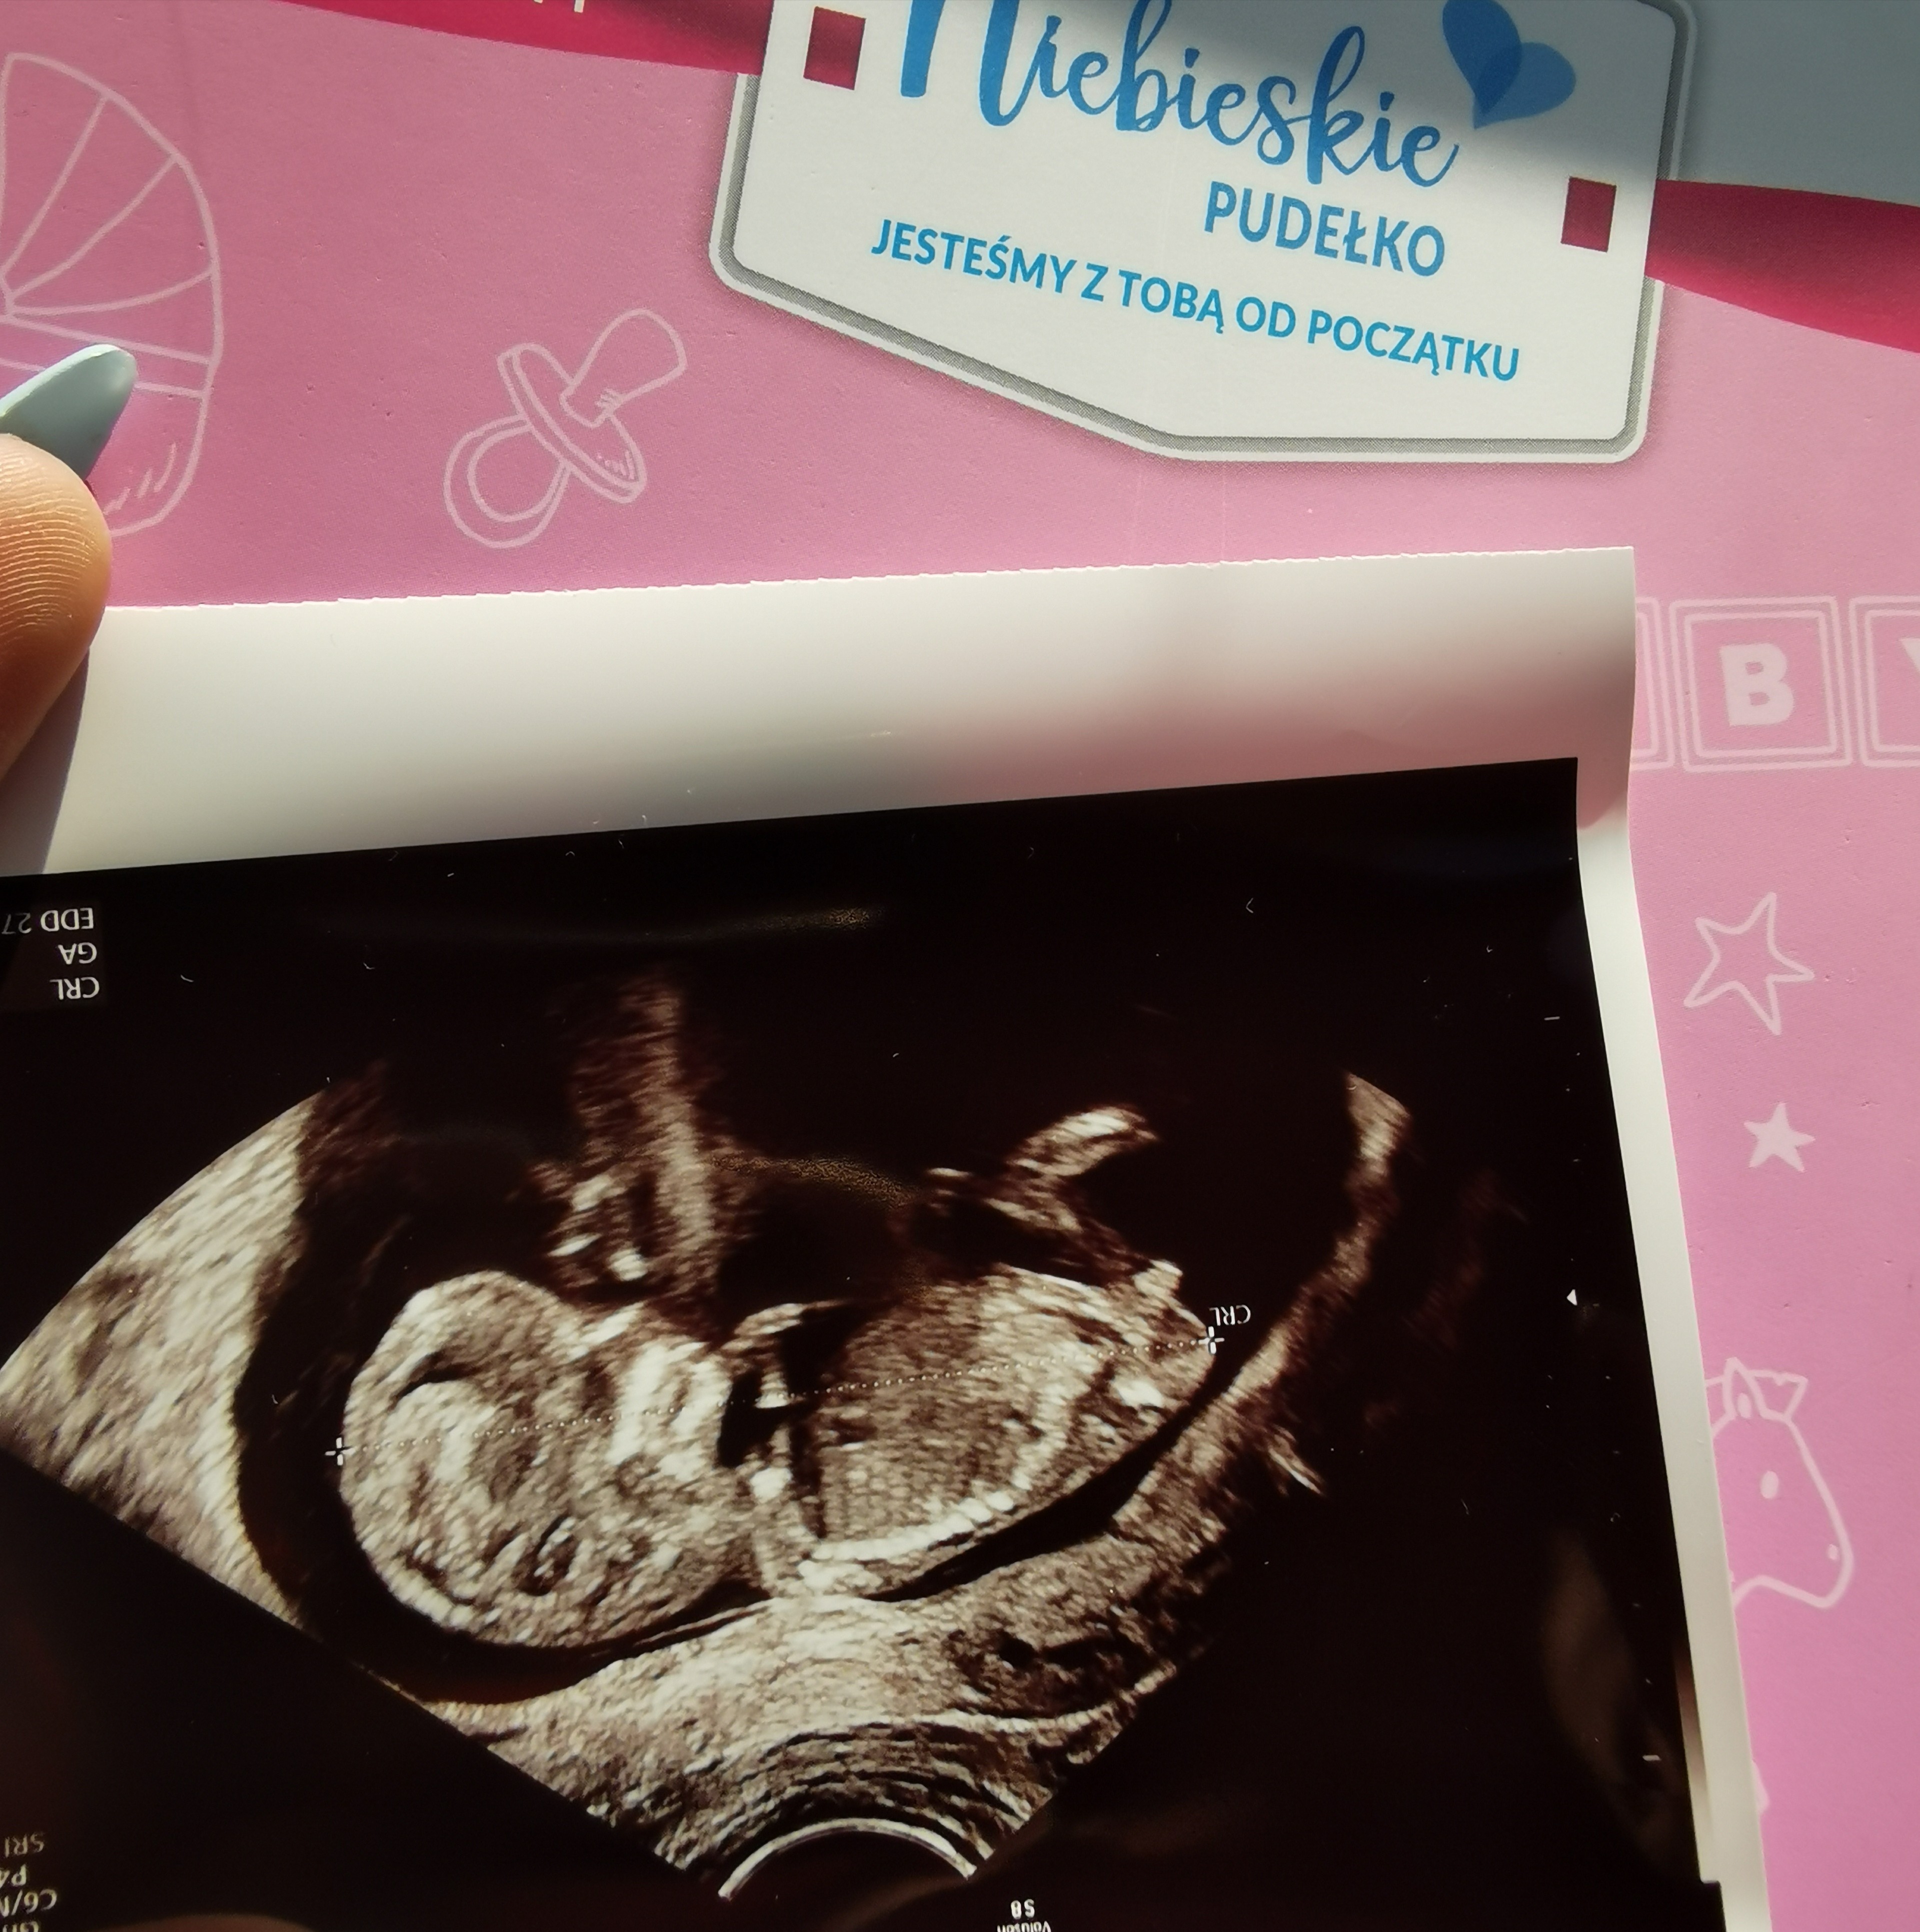

Czy widać tu płeć dziecka?

Cześć dziewczyny czy na tym zdje iu usg widać już płeć dziecka?

• IMG_20200916_113831.jpg